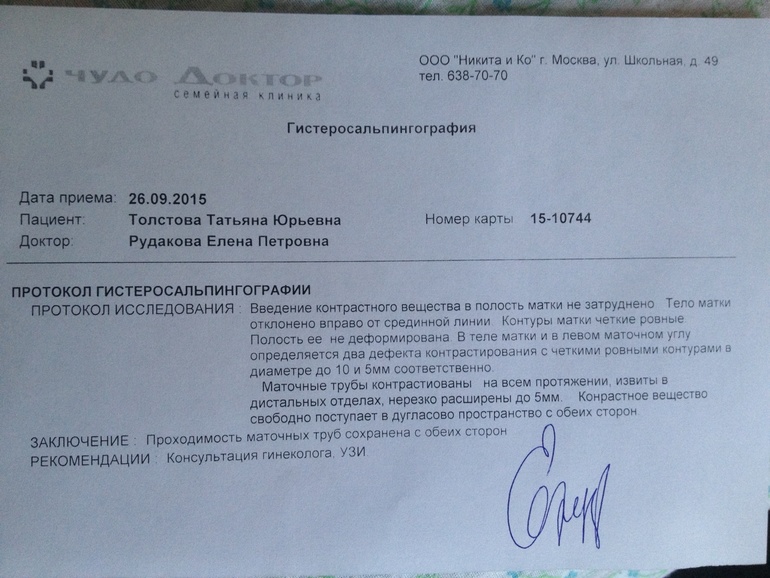

Гистеросальпингография: описание и фотографии

.jpg)

Раздел: Кадры дня